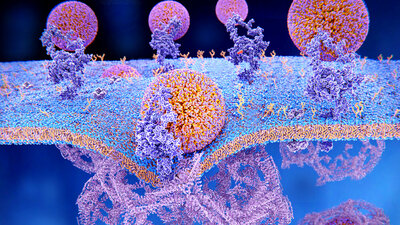

Fettstoffwechselstörungen

Ungünstige Blutfettwerte schaden den Gefäßen. Oft lassen sie sich mit bestimmten Maßnahmen verbessern. zum Artikel

Cholesterin und andere Blutfette

Enthält das Blut zu viel schlechte Fette wie Cholesterin und Triglyzeride, steigt das Risiko für Herzinfarkt und Schlaganfall. Welche Werte empfohlen sind. zum Artikel

Familiäre Hypercholesterinämie

Die erblich bedingte Fettstoffwechselstörung kann schon in jungen Jahren zu Herzinfarkt und Schlaganfall führen. Ursachen, Symptome und Therapie. zum Artikel